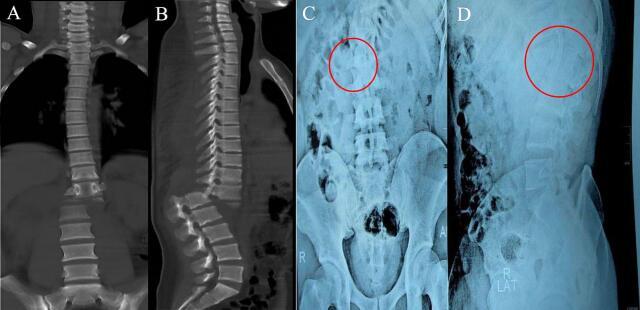

A 21-year-old man had multiple traumas after having a traffic injury, pain and numbness were positive during physical examination, especially in both lower limb. A radiography examination shows that the patient had total spinal cord transection and anterior spondyloptosis in T12 until L1 segment. Additional examinations found minimal renal and liver contusion including the ischemic bowel. The interbody fusion procedure was chosen as our therapeutic modalities.

一名21岁男性在交通伤后受到多处创伤,体格检查时疼痛和麻木呈阳性,尤其是双下肢。X线检查显示患者在T12至L1节段有完全性脊髓横断和前位椎体滑脱。进一步检查发现有轻微肾和肝挫伤以及缺血性肠损伤。选择椎间融合手术作为我们的治疗方式。